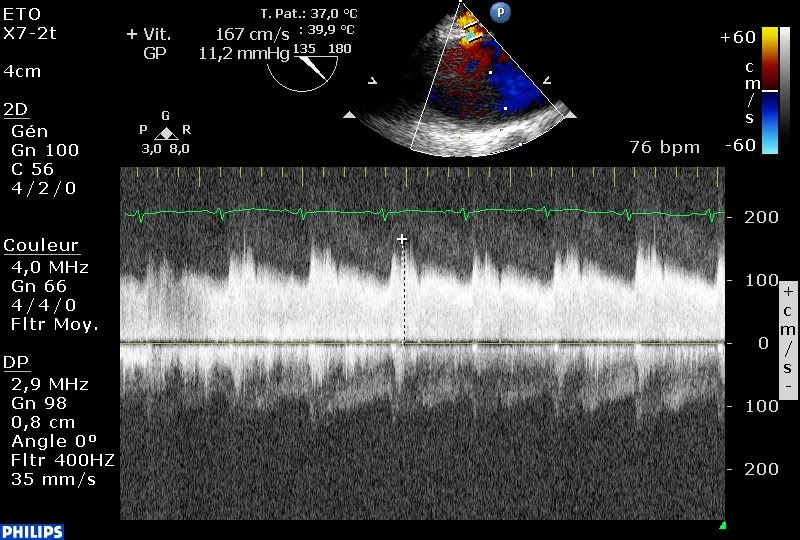

L’ETO retrouve sur la face postérieure de l’aorte un petit flux émergant d’un ostium de 3 mm.

Le flux est en fait un flux d’artériole à basse vitesse et avec une composante diastolique, et non un flux continu de shunt arterio-veineux comme le suggérait l’ETT. Il ne s’agit donc clairement pas d’un canal artériel persistant, les vélocités sont trop faibles, la localisation n’est pas la bonne, et le flux ressemble à une branche périphérique de l’aorte.